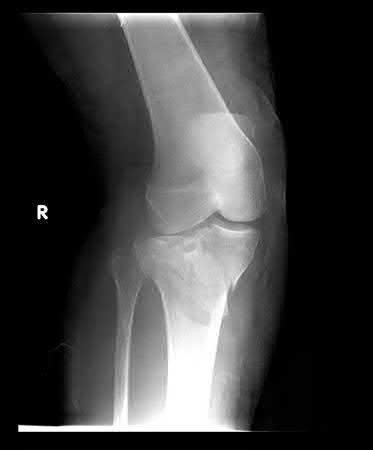

A 63-year-old patient presents with right ankle pain after a fall down four stairs. Figures A and B are the radiographs of the injury. The patient reports a history of diabetes mellitus type 2 and peripheral neuropathy with a most recent hemoglobin A1c of 9.8. The injury is

reduced and placed in a well-padded bivalved cast. The patient is then discharged with outpatient follow-up without DVT prophylaxis. Twelve weeks later, the patient presents to the clinic for the first time in the same bivalved cast. The has remained non-weight bearing and the bottom of the cast confirms this. What is the expected outcome at this point?

Figure A demonstrates an AP radiograph of a bimalleolar ankle fracture. Figure B demonstrates a lateral radiograph of a bimalleolar ankle fracture.